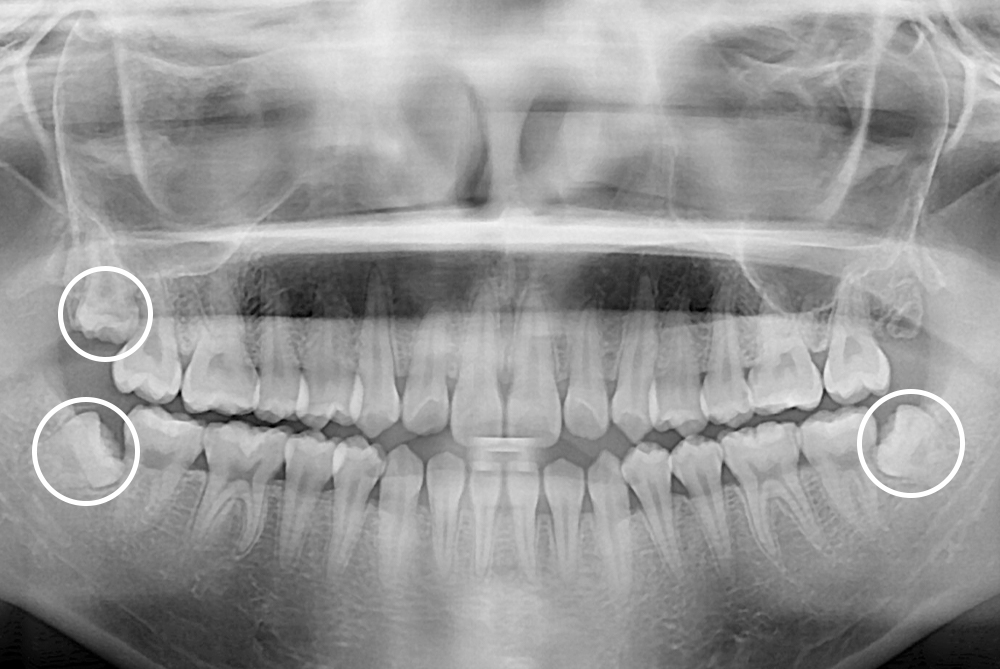

[사랑니] 매복 사랑니 발치

치료전 : 2019-08-12

세종치과는 구강악안면외과학 박사이신 원장님이 발치하는 치과입니다.